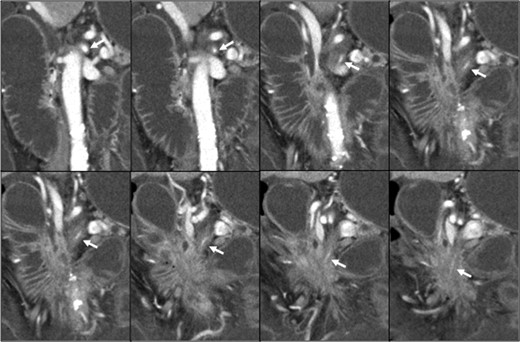

Contrast-enhanced abdominal computed tomography (CT) revealed a 48 × 28 mm mass in the pancreatic head that had invaded the whole circumference of the SMA. The SMA was occluded by the invasion of pancreatic cancer, and almost all of the small intestine was dilated with a very thin wall that was not enhanced (Figs 1 and 2). We diagnosed the patient with peritonitis and extensive necrosis of the small intestine due to SMA occlusion by the invasion of pancreatic cancer.

(a) Contrast-enhanced CT revealed a 48 × 28 mm mass in the pancreatic head (white arrow). Extensive intestine became ileus. (b) In the lower abdomen, the intestine showed no contrast effect, suggesting intestinal necrosis.

Pancreatic head cancer invaded the whole circumference of the SMA (white arrow), and the SMA showed stenosis and occlusion.